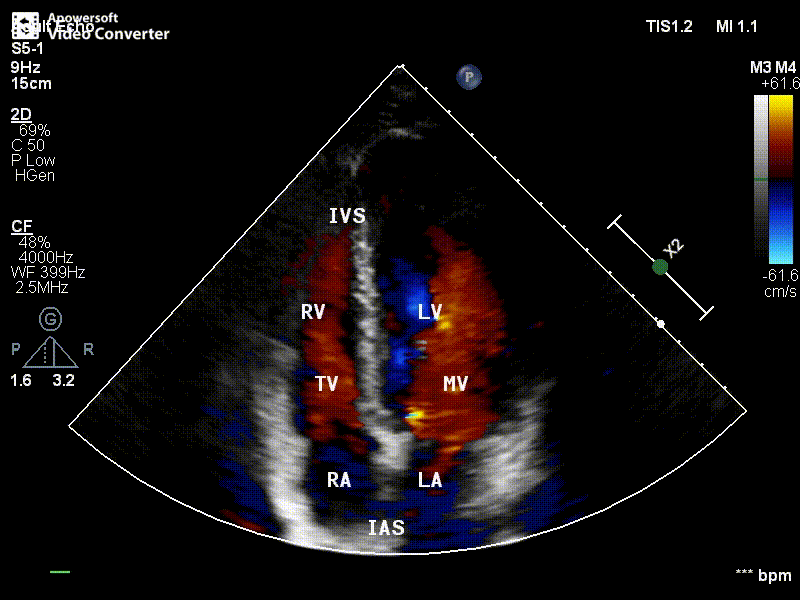

第五节 彩色多普勒

一、CDFI信号输出

红色:正向流

蓝色:反向流

绿色:紊乱程度

二、与频谱多普勒的对比

1、频谱多普勒:定量

彩色多普勒:定性

2、频谱多普勒:不直观

彩色多普勒:直观